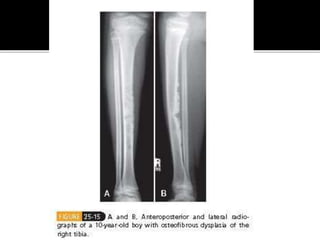

 A.K.A Campanacci disease

 Ossifying fibroma of long bones

 Common 2nd-3rd decade of life – usually

affecting the tibia and fibula

 Presentation – Asymptomatic unless there’s a

pathological fracture – anterior bowing.

 Radiologically – Multicentric radiolucent

lesions of the cortex of the tibia

 Histologically – Irregular trabeculae with

prominent osteoblastic rimming in a loose

fibrous stroma

 Treatment – Observation, Fractures usually

non-operatively, deformity correction.